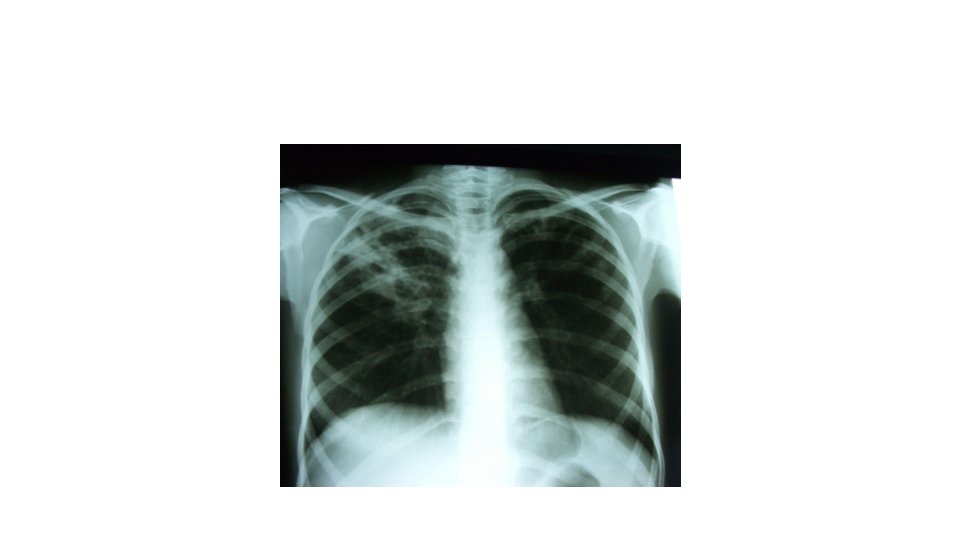

Tuberculose • Infiltrat Opacités micro et macro nodulaires confluentes par endroits cernant des clartés correspondant à une perte de substance réalisant l’aspect dit ulceéro nodulaire